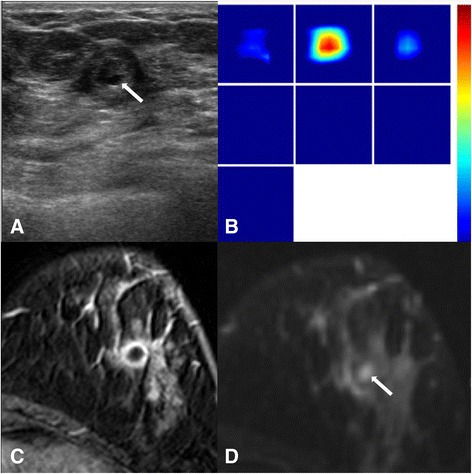

Between the THC and DCE-MRI parameters, only THC and SER showed a weak correlation with statistically marginal significance (r = 0.303, p = 0.058, Table 2). A higher total hemoglobin concentration was correlated with a more rapid washout rate (Fig. 1). There was no statistical significance in the correlation of THC and other two DCE-MRI parameters (r = −0.237 with Ktrans,p = 0.157; r = −0.218 with kep, p = 0.195). Fig. 2 illustrates one example of discordant findings between DCE-MRI and THC; while an unenhanced necrotic core is clearly noted on MRI, a high homogeneous THC map is shown on US-DOT. The mean and standard deviation value for each parameter are shown in Table 3.

Understanding the tumor microenvironment for angiogenesis can be complicated, and results obtained using different methods may not be well correlated. For example, although US-DOT, Color Doppler flow imaging, and DCE-MRI are all based vascular properties for measurements, Color Doppler imaging shows no significant correlation with microvessel counts [ref. 45], while some DCE-MRI parameters were reported to be correlated with microvessel density but not specifically with VEGF, a potent factor to stimulate angiogenesis [ref. 46]. Another major reason leading to the poor correlation of parameters is the high heterogeneous nature of the tumor. In this study, for DCE-MRI we included all enhanced tumor tissues from multiple imaging slices as ROI to evaluate kinetics on MR imaging, therefore, it is more like a “whole tumor analysis” approach. In US-DOT the maximum THC value in the ROI box was obtained and used for analysis, thus it is more like a “hot spot analysis” approach. Therefore, it is unlikely to have a high correlation between parameters obtained from “whole tumor” and “hot spot” analyses. However, it was not possible to do co-registered regional analysis due to the diffuse nature of the optical imaging. Optical imaging is very sensitive to the depth information, and tissues near the sensitive region of optical fibers will have more contribution to the measurement results. For example, as the case illustrated in Fig. 2, while DCE-MRI clearly shows a necrotic/cystic core, THC maps shows an averaged high blood volume, presumably due to the sensitivity to the strongly enhanced tissue near the surface closer to the source and detector fibers.